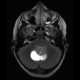

Teratoid tumor

An atypical teratoid rhabdoid tumor (AT/RT) is a rare tumor usually diagnosed in childhood. Although usually a brain tumor, AT/RT can occur anywhere in the central nervous system (CNS), including the spinal cord. [Source: Wikipedia ]